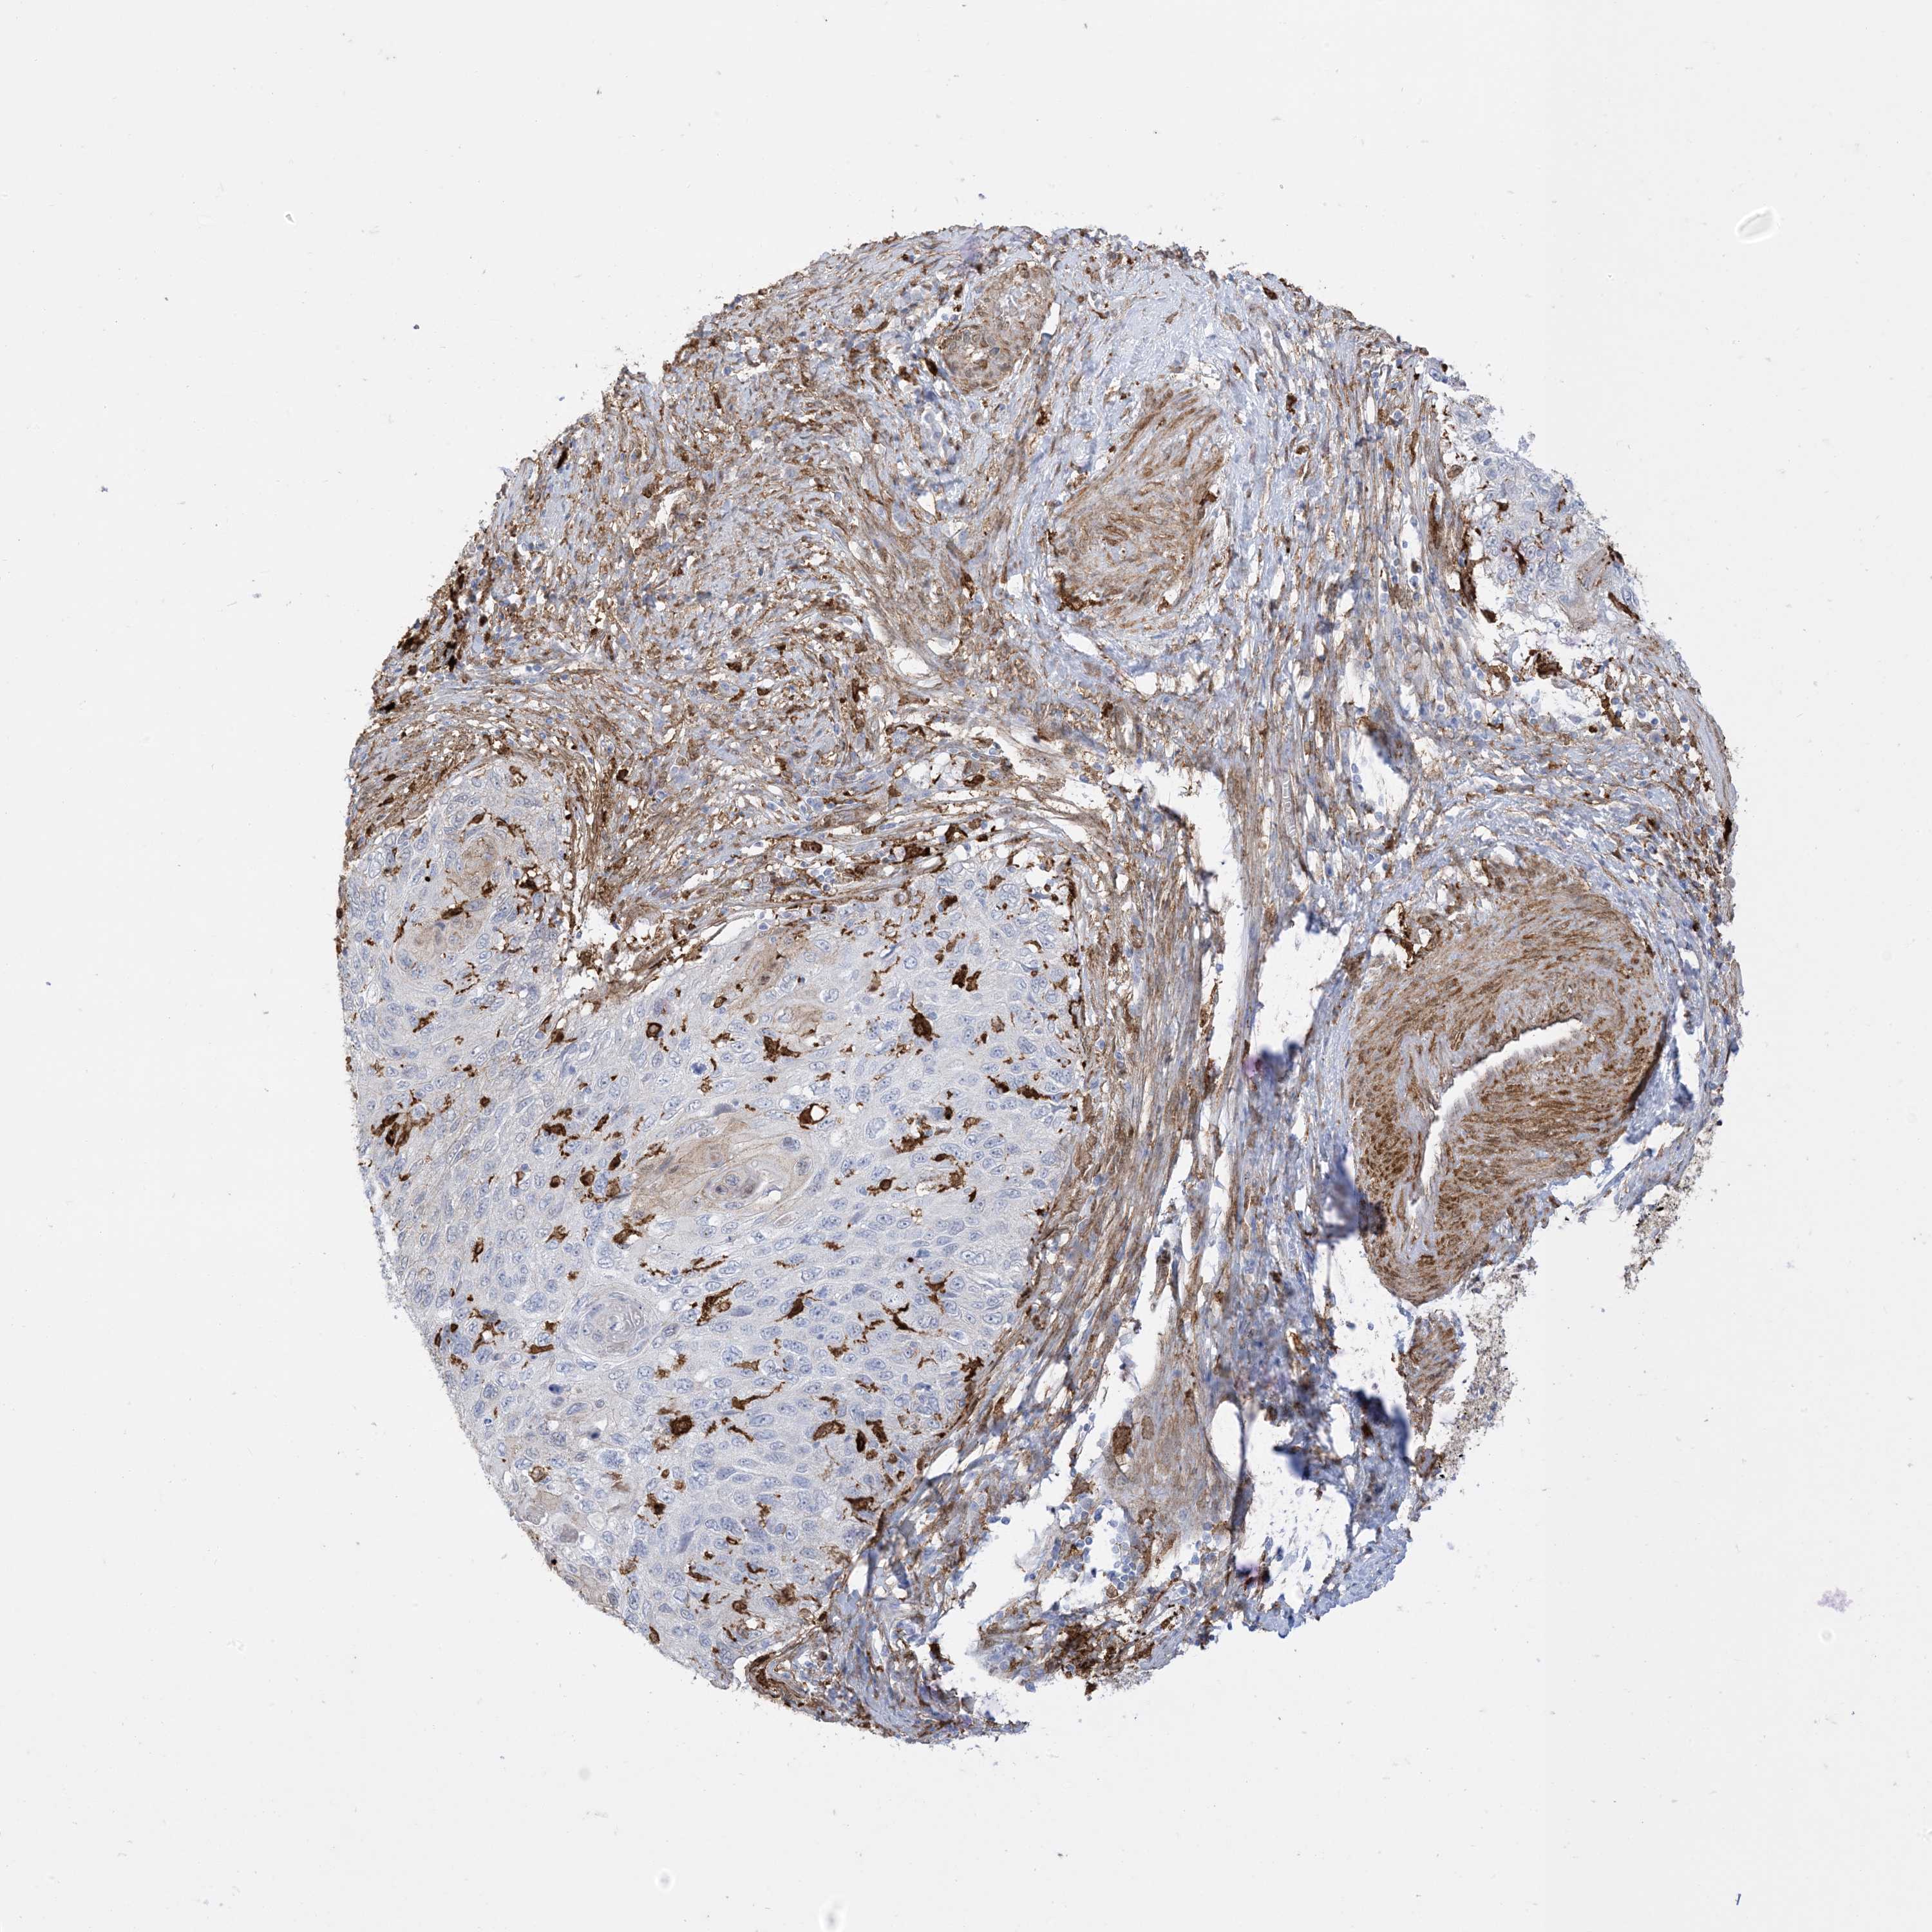

CERVICAL CANCER - Protein expressioni

A mouse-over function shows sample information and annotation data. Click on an image to view it in a full screen mode. Samples can be filtered based on level of antibody staining by selecting one or several of the following categories: high, medium, low and not detected. The assay and annotation is described here.

Note that samples used for immunohistochemistry by the Human Protein Atlas do not correspond to samples in the TCGA dataset.

Antibody stainingi

Antibody staining in the annotated cell types in the current human tissue is reported as not detected, low, medium, or high, based on conventional immunohistochemistry profiling in selected tissues. This score is based on the combination of the staining intensity and fraction of stained cells.

Each image is clickable and will lead to virtual microscopy that enables deeper exploration of all samples and also displays staining intensity scores, fraction scores and subcellular localization as well as patient and tissue information for each sample.

Antibody HPA054026

Antibody CAB010823

Antibody CAB016728

Antibody CAB036009

Adenocarcinoma, NOS